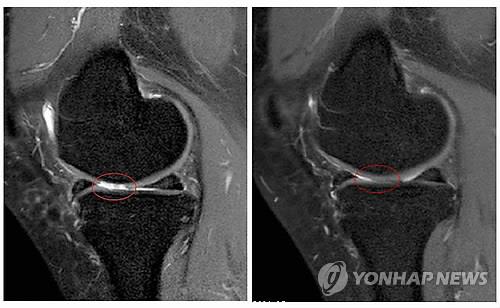

세포치료·면역요법 국제컨소시엄(International Consortium for Cell Therapy and Immunotherapy)의 야로슬라프 미할레크 박사는 자가지방세포 이식이 퇴행성 관절염의 증상을 완화하고 손상된 관절을 일부 회복시키는 효과가 있다는 임상시험 결과를 발표했다고 의학뉴스 포털 메디컬익스프레스(MedicalXpress)가 16일 보도했다.

퇴행성 관절염 남녀환자 1천114명(평균연령 62세)을 대상으로 진행된 임상시험에서 각자에게서 떼어낸 지방조직 샘플에서 기질혈관분획(SVF)세포를 채취, 손상된 관절에 이식하고 12~54개월 동안 지켜본 결과 이 같은 효과가 나타났다고 마할레크 박사는 밝혔다.